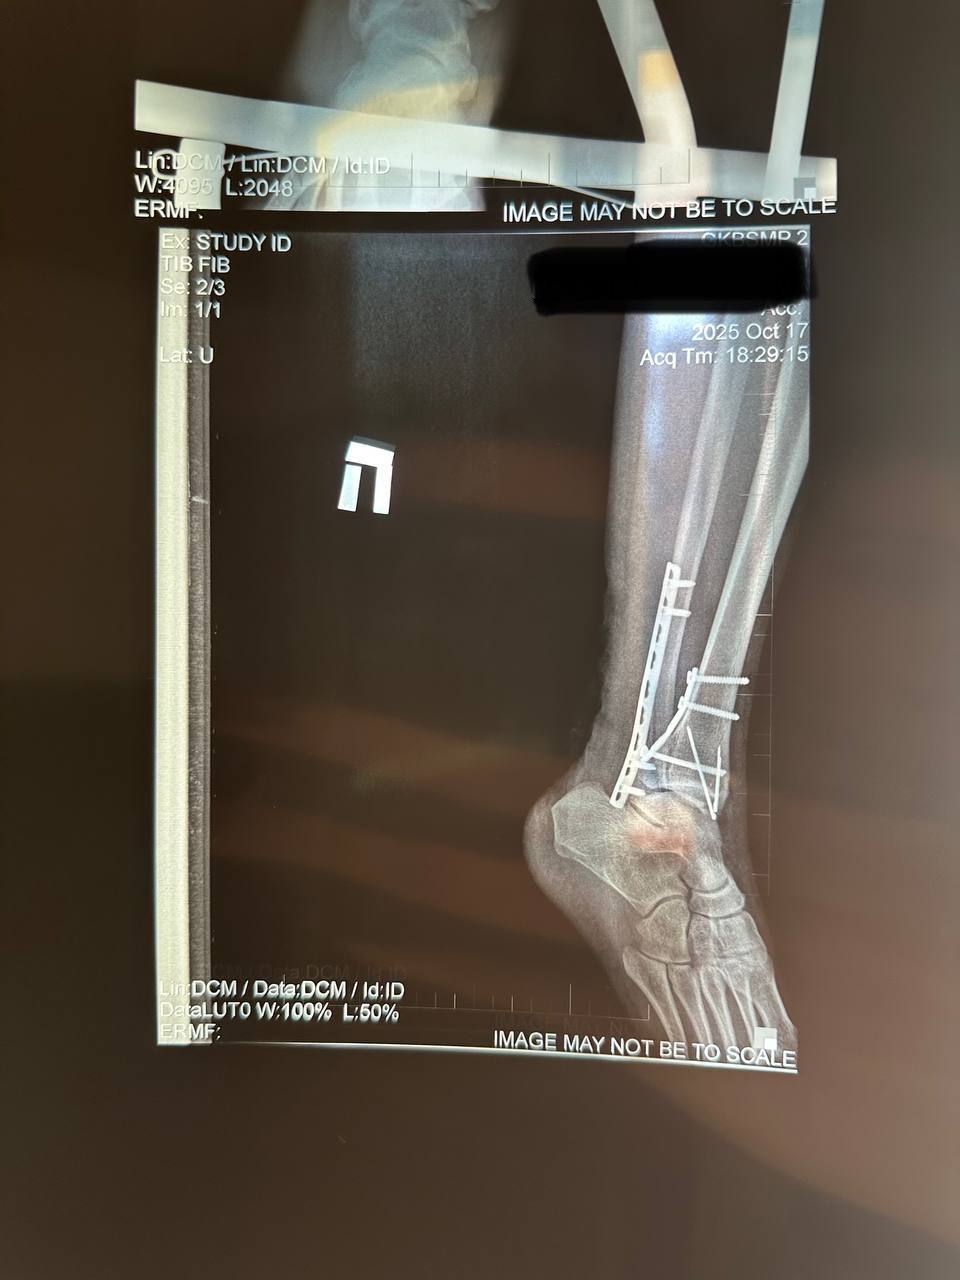

На данный момент прошло 5 месяцев с момента травмы. Мне установили 2 пластины, 7 винтов и 2 спицы в правую ногу. Боль уже почти не мучает, но я до сих пор хожу с тростью и прохожу реабилитацию по восстановлению двигательных функций.